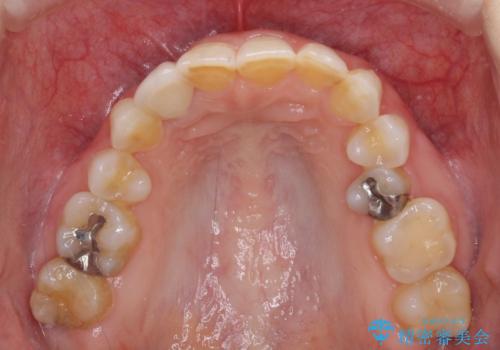

- 前歯のクラウン周りに歯肉が腫れていることを気にして来院された患者様です。

元々磨き残しによる歯肉の腫脹がありましたが、クラウンが歯肉深くに装着されていたため、特に腫脹が目立っていました。

仮歯に置き換えた際に歯周外科処置を行い、歯肉の腫脹が落ち着いたことを確認してオールセラミッククラウンにて補綴することとしました。

外科処置後の痛みを気にしていましたが、小規模の処置であったため、痛みを感じることはほとんどありませんでした。

気になっていた腫脹がなくなり、患者様には大変満足していただきました。